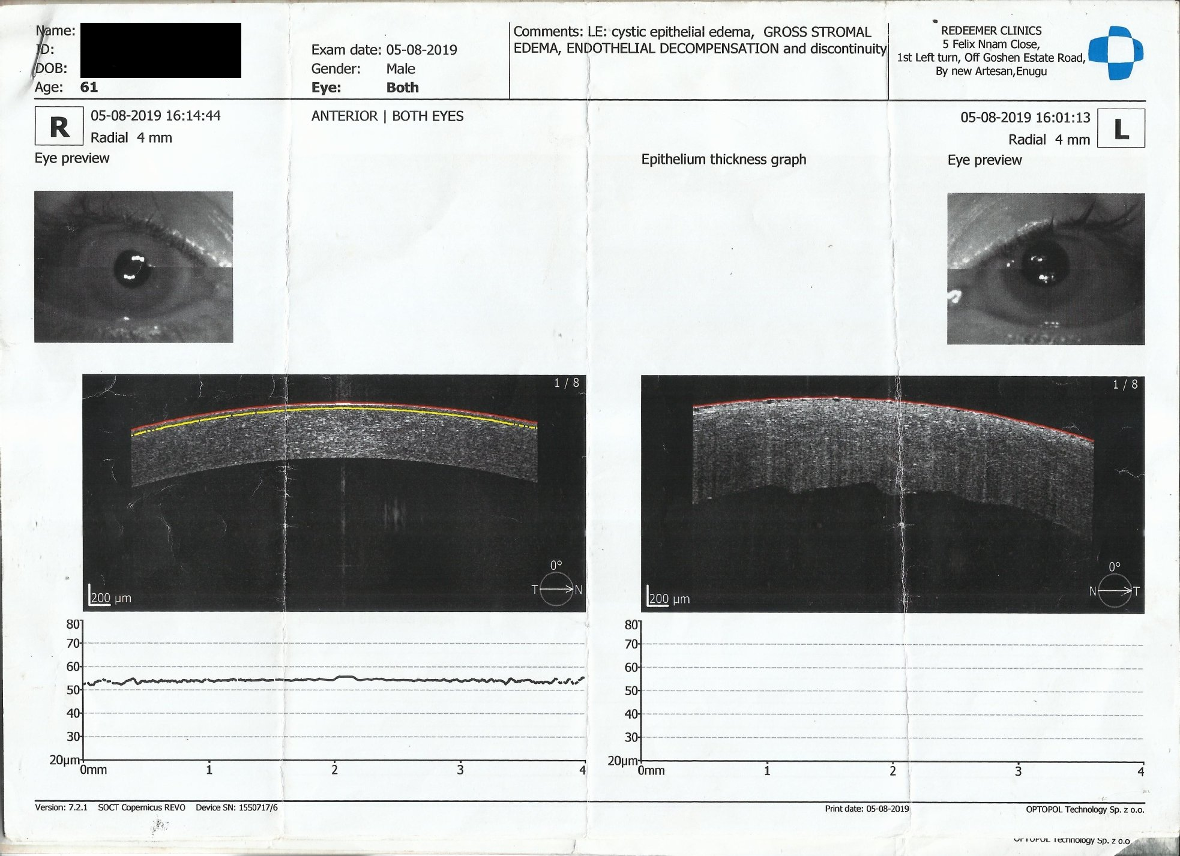

On the first post-operative day, the patient complained of reduced vision. The visual acuity was 6/36; there was a low diffuse bleb superiorly; the anterior chamber was formed but the patient had a generalized Descemet’s membrane folds with no pain; and the intraocular pressure was 15.6 mmHg. There were no cells, no flare, no fibrin, no hypopyon, the pupil was mid-dilated, the iris was normal, and no reaction in the vitreous was present. On the tenth day post-operatively, visual acuity reduced further to 1/60. There was an intense cornea edema (Figure 1 [Fig. 1]). He was treated with topical dexamethasone two-hourly, sodium chloride three-hourly, timolol twice daily, and a systemic oral acetazolamide 250 mg eight-hourly and prednisolone 20 mg twice daily for four days and tapered off over the next three days. Anterior segment OCT showed gross stromal edema (Figure 2 [Fig. 2]). During the follow-up visit in the fifth month, the patient had pain and subconjunctival hemorrhage which later resolved. However, cornea edema persisted, and bullous keratopathy developed, and the patient was referred to another center for penetrating keratoplasty, but he declined any other further intervention. Presently IOP is 8 mmHg and the patient is continued on topical hydroxypropyl methylcellulose eight-hourly.

Figure 2: Anterior segment optical coherence tomography showing gross stromal edema